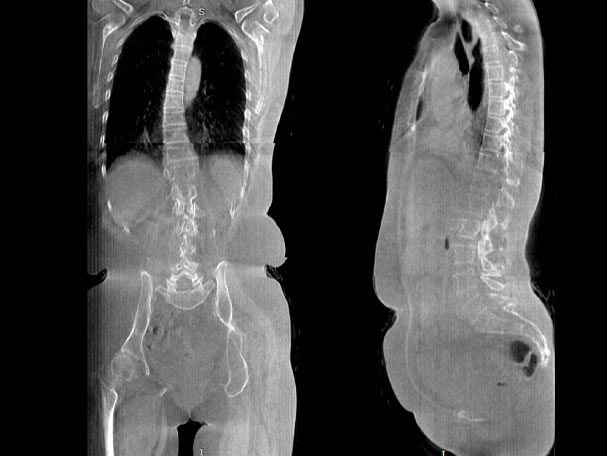

· 補(bǔ)位CT,提供負(fù)重位三維影像

· 引領(lǐng)普放走向三維精準(zhǔn)診斷時(shí)代

填補(bǔ)常規(guī)CT/MR空白

助力術(shù)前規(guī)劃和術(shù)后評(píng)估

頸椎

腰椎